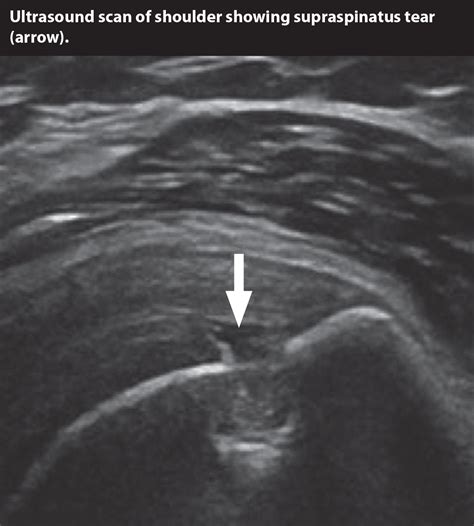

Understanding Shoulder Anatomy and Ligament Tears

Diagram showing the shoulder joint and surrounding ligaments

The shoulder is essentially a ball-and-socket joint, but it is held together by a intricate network of tissues, including tendons, muscles, and ligaments. Ligaments are tough, fibrous bands of connective tissue that connect bone to bone. Their primary purpose is to provide stability to the joint and prevent it from moving beyond its normal range.

A torn ligament in shoulder, often referred to as a shoulder separation or instability, occurs when these bands are overstretched or ruptured. Unlike a muscle strain, which involves the tissue that moves the bone, a ligament injury affects the tissues that keep the bones properly aligned within the joint socket.